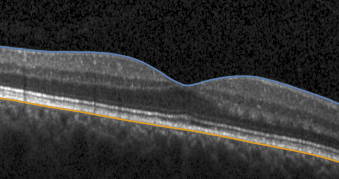

Images - The scanning laser ophthalmoscopy (SLO) image

- The segmentation data for different retina layers (ILM, RPE) when provided in the HEYEX Raw file